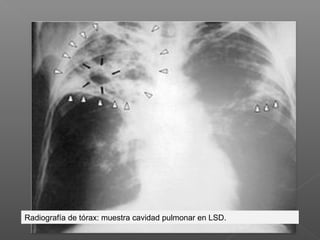

Radiografía de tórax: muestra cavidad pulmonar en LSD.

Radiografía de tórax:muestra cavidad pulmonar en LSD.